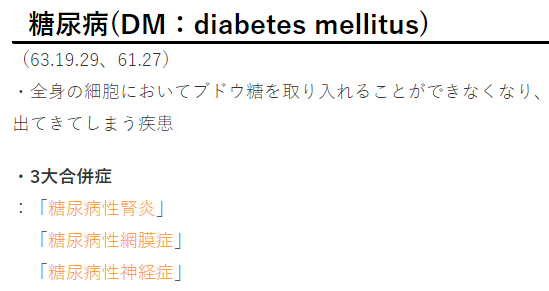

| 膵臓 | α細胞 | ★グルカゴン | ・肝臓に貯蔵されているグリコーゲンの分解促進 | |

| β細胞 | ★インスリン | ・グリコーゲンの合成促進 ・細胞の糖取り込み(糖の消費)を促進 ・過剰→「低血糖症」 ・欠乏→「糖尿病」 |

||

| δ細胞 | ★ソマトスタチン | ・グルカゴン、インスリンの分泌抑制 | ||